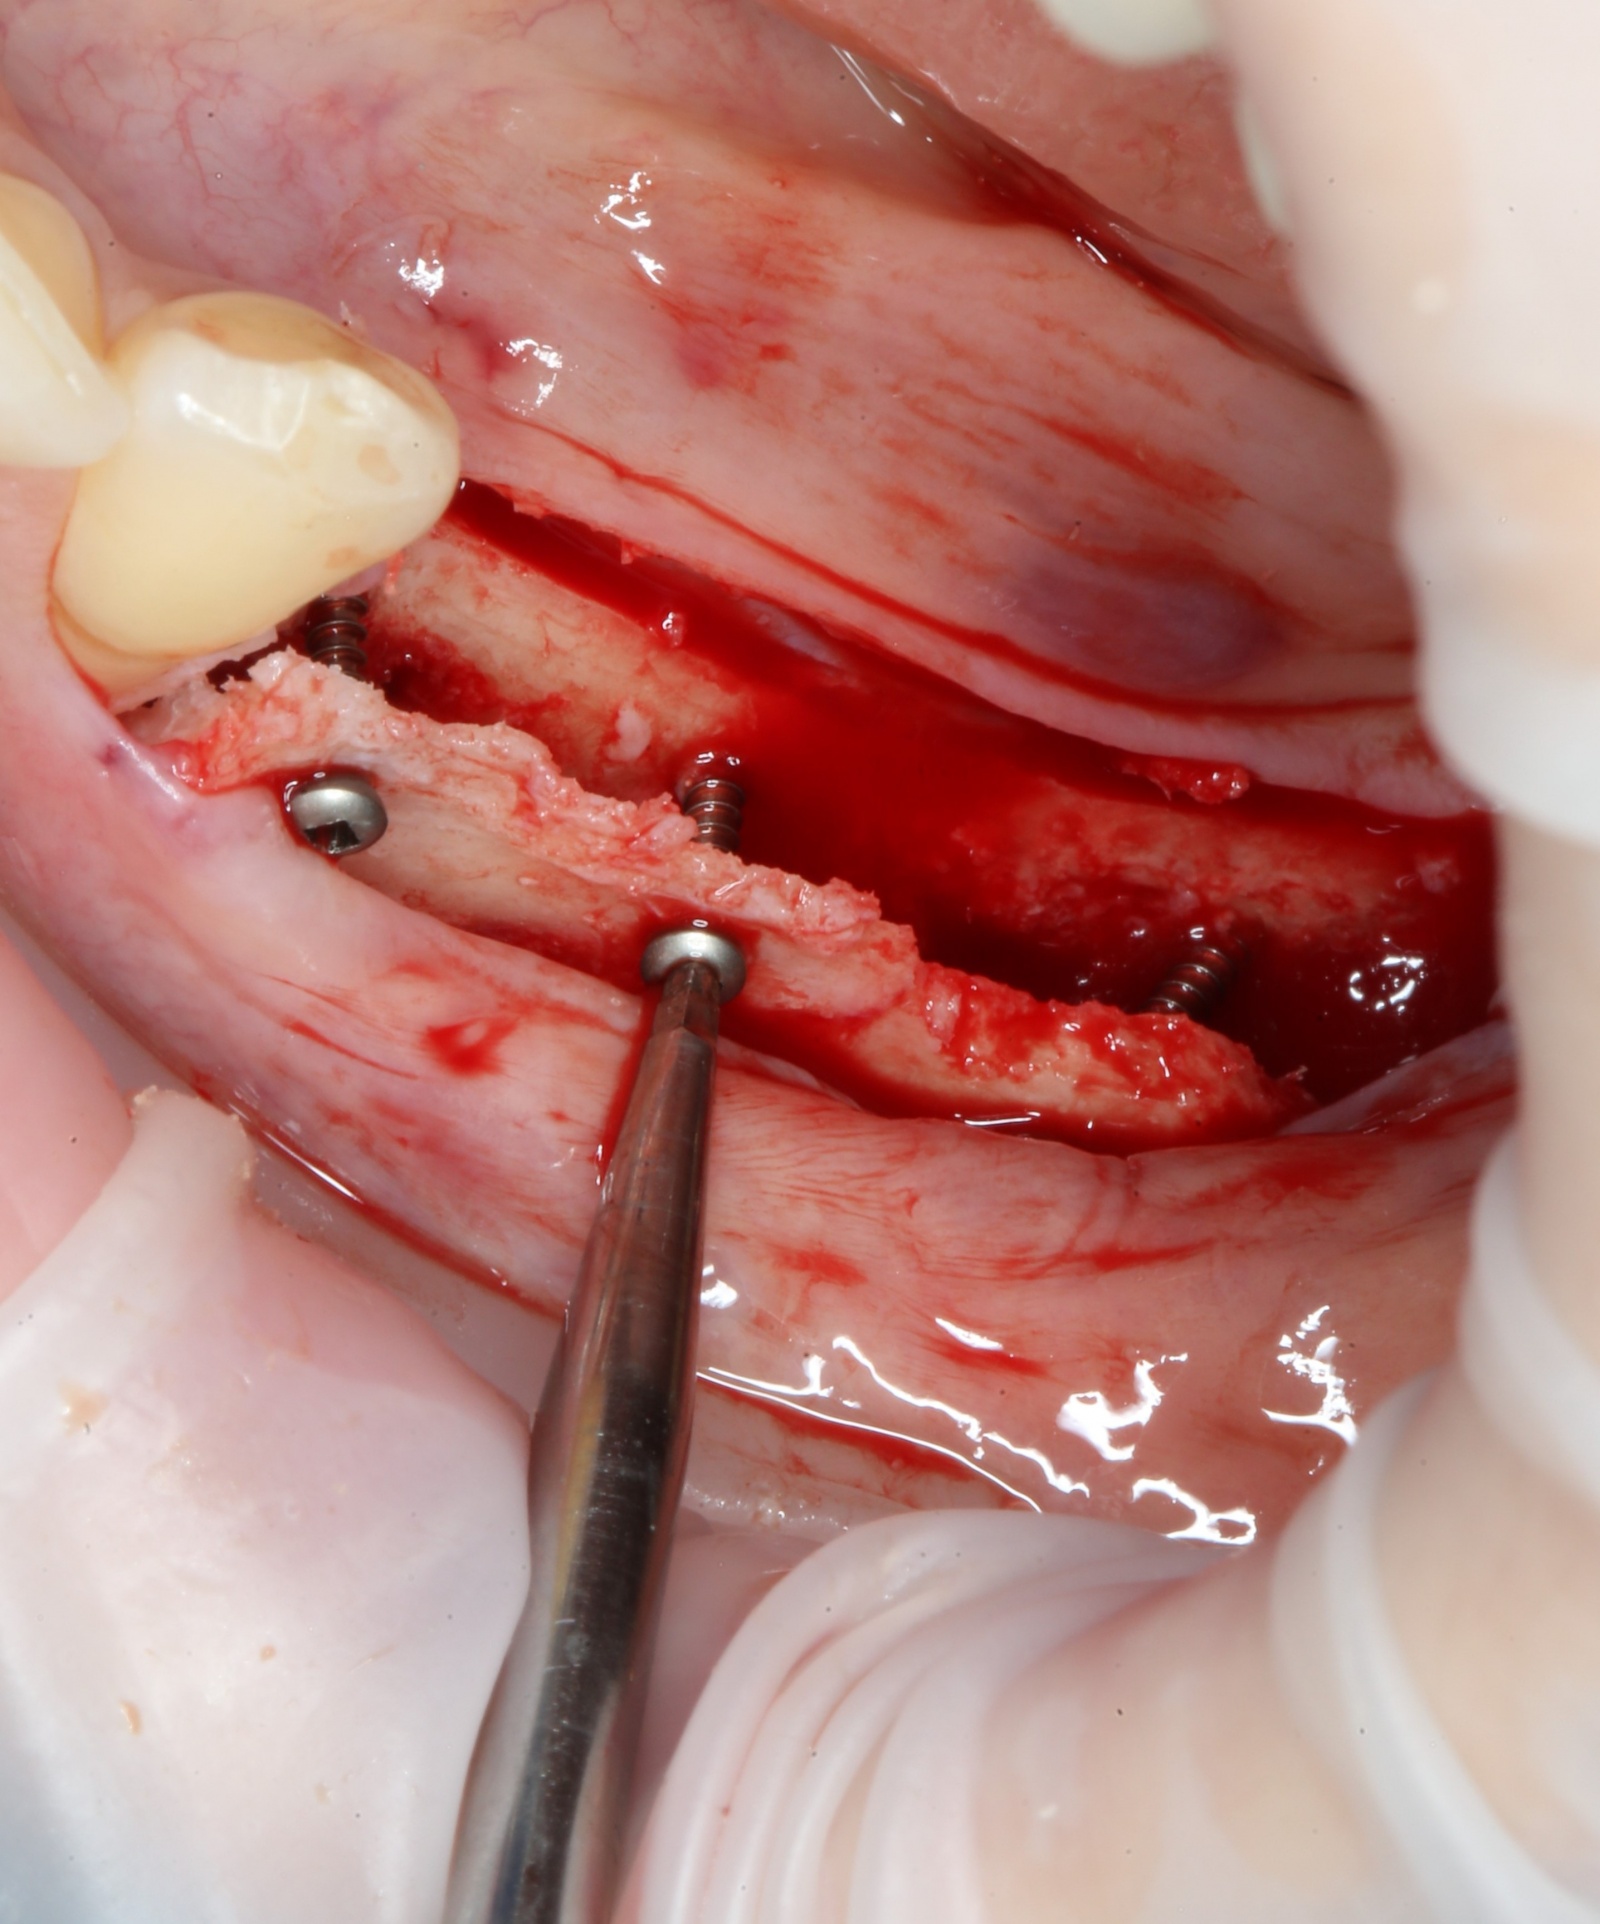

Для фиксации костного фрагмента, чтобы тот в дальнейшем не отвалился, используются специальные винты.

С учётом того, что это не саморезы, для начала необходимо сделать отверстия в кости:

Получаем вот такой короб:

Далее необходимо заполнить промежуток между двумя фрагментами костным материалом.